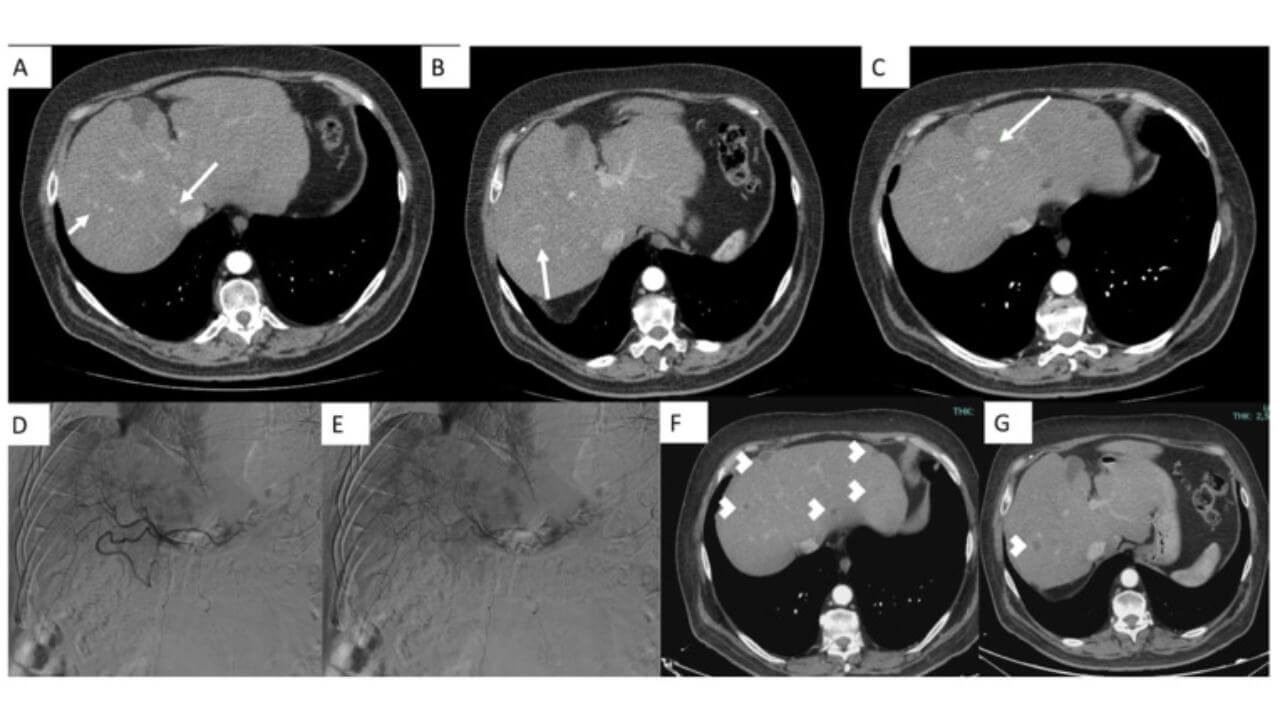

Embolization is a low-traumatic intervention, the purpose of which is to block the blood vessels feeding the tumor. As a result, cancer cells stop receiving nutrients and die quickly. In Germany, two main types of embolization are commonly used for treating liver cancer: chemoembolization and radioembolization.

Transarterial chemoembolization is the most common procedure, combining two treatment methods: embolization and local chemotherapy [5]. The use of this procedure for stage 4 liver cancer involves arterial lumen closure with microspheres containing chemotherapy drugs. They are gradually released over several weeks, creating a high concentration of drugs in the hepatic parenchyma and inhibiting the growth of neoplasms. After the procedure, the primary tumor can drastically decrease in size, sometimes by tens of times. Unlike standard chemotherapy for the fourth stage liver cancer, the patient does not experience any severe side effects after chemoembolization.

The radioembolization technique differs from chemoembolization in that the microspheres are saturated not with drugs, but with radioactive substances. It has been used as a treatment option for inoperable liver cancer since 2016.

Ablation is the destruction of cancer tissue using various types of energy or chemicals (alcohol, acetic acid) [6]. The procedure is usually combined with chemoembolization and other treatment methods.

Until recently, the most popular procedure was radiofrequency ablation, which involved the insertion of a probe into the liver tissue, heating it up, and therefore, leading to the destruction of the metastatic neoplasms. However, German hospitals increasingly use microwave ablation. This is a more progressive technique with several advantages. It appeared simultaneously with radiofrequency ablation, but could not be introduced into clinical practice for technical reasons. Rather, compact devices for microwave ablation appeared only a few years ago. They can be inserted into the lump through a puncture in the abdomen. The essence of the technique is that an antenna, which emits electromagnetic energy, is used to heat the tumor.